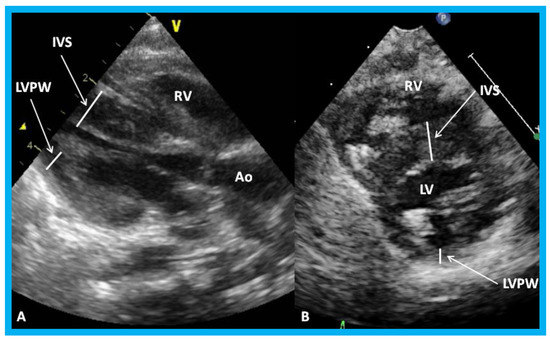

Figure 25. Parasternal long (A) and short (B) axis views of the left ventricle (LV) demonstrating markedly thickened interventricular septum (IVS) in an infant of a diabetic mother. Ao, aorta; LVPW, LV posterior wall thickness; RV, right ventricle.